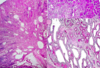

What do you see here?

Acute interstitial nephritis

What type of immune reaction is elicited in AIN?

- Cell-mediated immunity plays major role with activated T-cell infiltration and sometimes formation of granulomas

- Antibody mediated immunity may also play a role, especially in methicillin induced AIN

- Proliferation of interstitial fibroblast and matrix

- TGF-b plays critical role